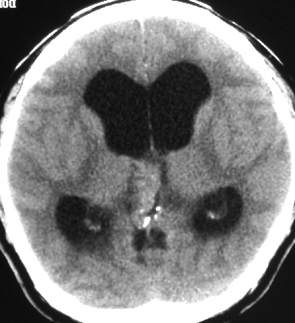

成人男性の松果体芽腫です。左のCTでは白く見える石灰化があります。水頭症があって頭痛と嘔吐で発症しました。右のMRIでは腫瘍の形が丸くなくて周囲の脳に浸潤したり脳室の壁などにべっとり広がっているように見えます。悪性腫瘍の特徴的な像で,開頭手術をしても摘出できないことが判ります。松果体芽腫は悪性度が高くて(WHOグレード4),脊髄などに播種転移したりしますし,手術だけでは治りません。

腫瘍は定位脳手術で生検をしました。水頭症に対しては内視鏡で第3脳室開窓術を行なって症状を改善しました。左のMRIで水頭症が良くなっているのが判ると思います。それから,全脳脊髄に30グレイの放射線治療をして腫瘍局所には24グレイの照射を追加しました。同時にICE化学療法というのを6コースしました。右のMRIでは治療が終わって小さく固まった残存腫瘍が見えます。この残存腫瘍は第3脳室の壁にくっついていて摘出するリスクがとても高いと思いましたので,そのままずーっと10年間様子を見ていますが再発していません。でも,残存腫瘍がなんとか取れる時は徹底的に取ってしまった方が再発率は少ないといえます。